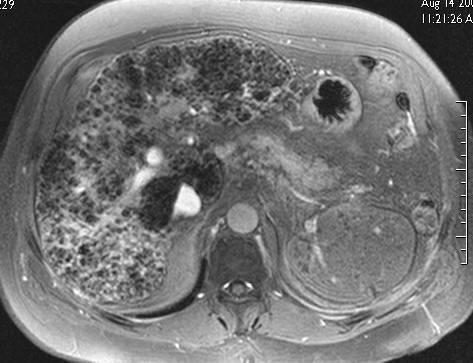

Cirrhose alcoolique avec fibrose irrégulière. Développement d'un foyer de condensation fibreuse plus dense dans le segment 7, respect relatif du lobe caudé et du lobe gauche. Interêt de l'endorem.

Séquence EG (alpha 70° ) 2 h 30 après perfusion d'endorem. Cette séquence est très sensible aux modification du T2* pour le parenchyme hépatique même en pondération T1 Le foie fonctionnel est en hyposignal et la fibrose en net hypersignal. L'interêt de garder un angle de bascule élevé est d'avoir un bon rapport signal bruit et de permettre une résolution élevée favorisant la visualisation des bandes fines de fibrose.